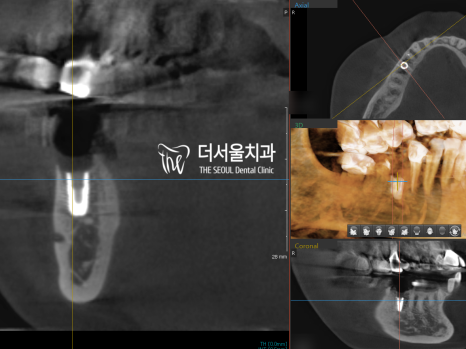

분석 위치에 딱 맞게 심어져 있는

모습을 확인할 수 있습니다.

좌측이 전, 우측이 후 사진인데,

정말 싱크로율 100%네요.

이후 충분한 골화가 진행된 것을

확인한 뒤에 어금니 크라운 제작과 함께

ISQ 측정 결과 튼튼하게

고정된 것이 확인되어

보철 제작을 진행할 수 있었는데요.

최종 파노라마 사진을 보면

올바른 교합, 맞물림으로 제작된

보철을 볼 수 있습니다.